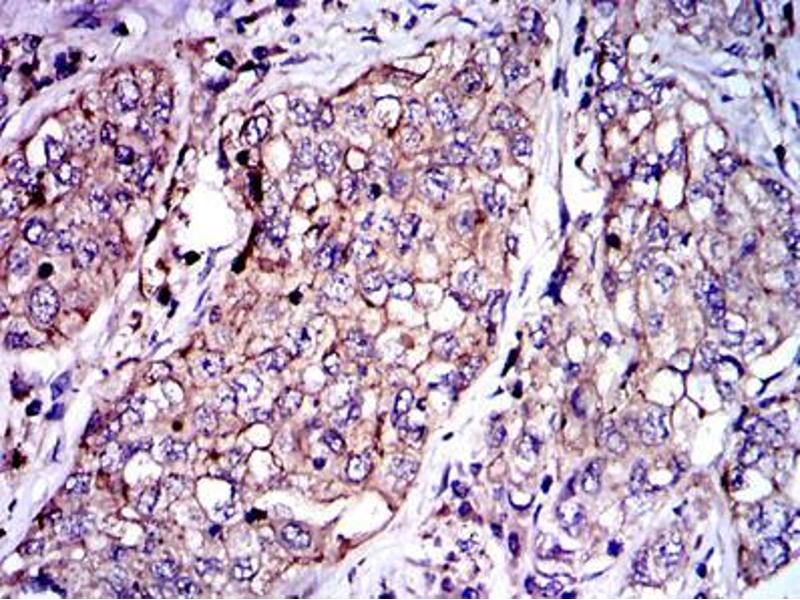

- PAI1 (SERPINE1) (Plasminogen Activator Inhibitor 1 (SERPINE1))

背景